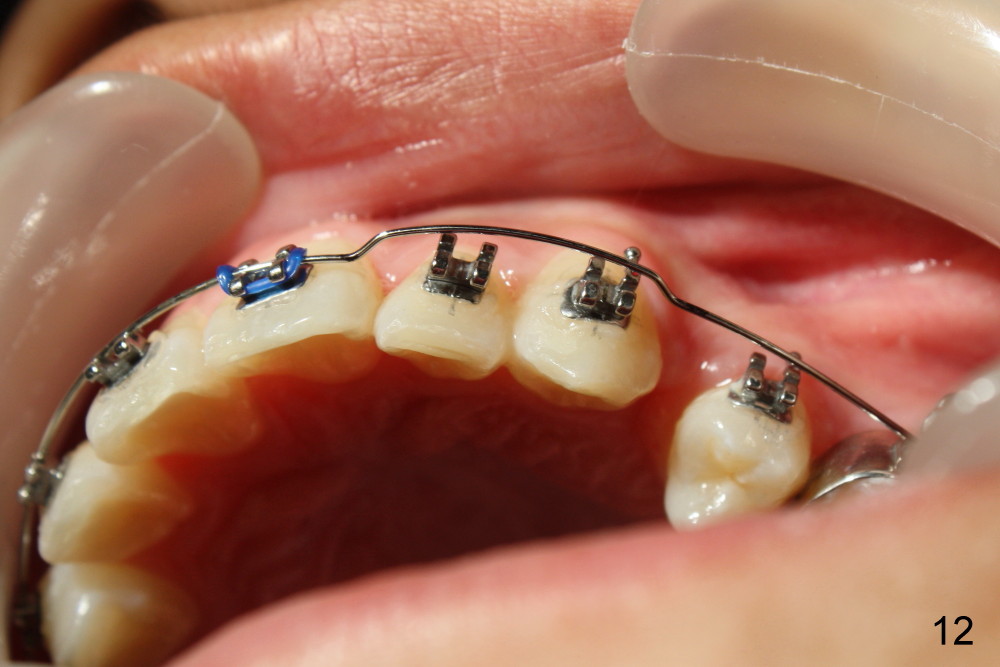

A 13-year-old boy has severe crowding (Fig.1-5). Four of the first bicuspids were extracted on 02/17/2014. Full mouth brackets or bands (except #18) were placed on 03/27/2014. Alignment improved 2 months later (Fig.11, 05/24/2014). The upper 18 ss wire was modified (Fig.12), and fixed with alastiks (Fig.13,14). One month later (07/01/2014), local alignment also improved (Fig.15); the upper modification is confined to one tooth.